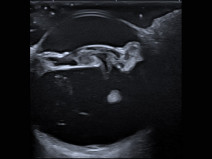

• Plan modulaire en échographie - Module de base d'échographie abdominale

Principes du plan modulaire d’échographie

Le plan de formation est composé d’un module de base d’échographie abdominale (2 jours), d’un module avancé en échographie abdominale pour être capable de reconnaitre les lésions abdominales les plus fréquemment rencontrées (2 jours). Pour celles et ceux qui souhaitent aller encore plus loin, nous proposons aussi 2 modules spécifiques, d’une j...

Du 4 au 5 septembre 2025

Carquefou (44470)

Imagerie Médicale

G.E.I.M.

1938